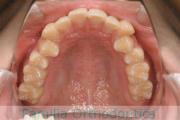

上の前歯の並びが気になるのできれいにしたい、ということで来院されました。マウスピース型矯正装置のひとつ、インビザライン/InvisalignR(薬機法および医薬品副作用被害救済制度の対象外)を用いて治療しました。

非抜歯で2年弱、20回程度の通院で治療が完了しました。

マウスピース矯正は、患者さんの協力に治療結果が左右されるところはリスクと言えるかもしれません。